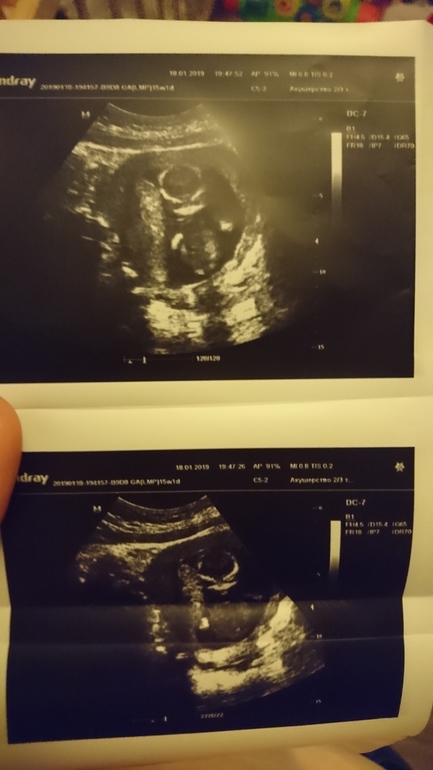

УЗИ, КТГ, доплерПервое узи 13 недель, второе- сегодня (16недель), пол не увидели, но предположил и, а вам как кажется?)

Знаю что по второму ничего не скажешь, но приложу))